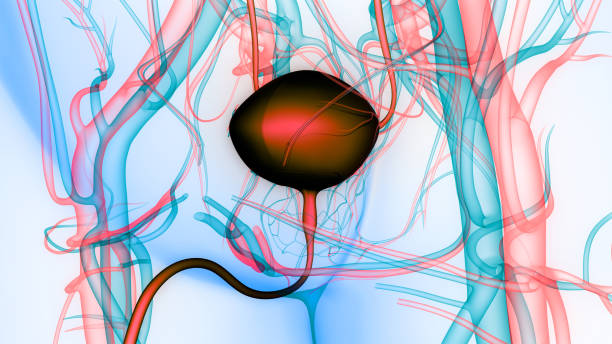

방광암은 초기에 증상이 뚜렷하지 않아서, 발견되기 전까지 오랜 기간 동안 증상이 없을 수 있습니다. 이로 인해 진단이 늦어져 치료가 어려워질 수 있습니다. 그러므로, 방광암의 초기증상을 잘 알고 있어야 증상이 나타났을 때 빠르게 대처할 수 있으며, 조기 발견과 치료로 인한 예후 개선 가능성이 큽니다. 또한 방광암은 흡연, 화학 물질 노출, 방광염 등의 위험 요인에 노출되면 발생할 가능성이 높습니다. 따라서 위험 요인에 노출되는 직업이나 환경에서 근무하는 사람들은 방광암에 대한 예방과 조기 발견에 더욱 신경써야 합니다.

방광암이 초기단계에서는 방광 내부에 종양이 형성되어 있을 수 있으며, 종양이 방광의 용량을 차지하여 소변의 양이 감소하게 됩니다. 이로 인해 소변을 보고나서도 만족스럽게 소변이 나오지 않는 느낌이 들 수 있습니다. 소변량의 변화는 개인마다 다를 수 있으며, 소변량의 감소가 지속된다면 의사를 찾아 상세한 검진을 받아야 합니다.

방광암이 발생하면 종양이 방광 내부에 있어 소변과 직접 접촉하게 되어 소변이 희고 탁해지거나 혼탁해질 수 있습니다. 소변이 투명하지 않고 탁해지는 것은 방광 내부의 종양이 성장하고 있는 것을 나타낼 수 있습니다. 이러한 증상이 지속되면 의사를 찾아 검진을 받아야 합니다.

방광암의 초기증상 중 하나로 소변에 섞인 혈뇨나 핏물이 나오는 경우가 있습니다. 방광 내부의 종양이 소변에 혈관을 침범하여 혈뇨가 발생할 수 있습니다. 소변에 섞인 혈뇨나 핏물이 나오는 경우에는 의사를 찾아 상세한 검진을 받아야 합니다. 이러한 혈뇨나 핏물이 지속되는 경우 진단과 치료를 위해 빠른 시일 내에 의료 전문가의 조언을 받아야 합니다.

방광암 초기증상으로 소변을 보는데 어려움이 있는 경우는 드물지만 발생할 수 있습니다. 방광암이 발생하면 방광벽에 종양이 생겨서 방광의 용량이 감소하게 됩니다. 이 경우 소변이 자주 나오지만 소량씩 방출되거나 소변을 가누기가 어려워질 수 있습니다. 소변을 보는데 어려움이 생긴다면 방광암 가능성이 있으므로 즉시 전문의를 방문하는 것이 좋습니다.

방광암 초기증상으로 복부에 압통이나 불편감이 있는 경우는 비교적 더 자주 발생합니다. 이는 종양이 방광 벽을 침범하고 근육을 늘리거나 복강 내 다른 기관에 영향을 미치면서 생길 수 있습니다. 이러한 증상은 방광암 이외에도 다른 병인에서도 나타날 수 있으므로 반드시 전문의의 진단을 받아야 합니다.

방광암 초기증상으로 하지나 발목 부근의 부종이 나타나는 경우는 드물게 발생합니다. 이는 방광암이 진행되면서 림프관에 침범하여 림프절에 암세포가 전이되어 생길 수 있습니다. 따라서 부종이 나타난다면 즉시 전문의의 진료를 받는 것이 중요합니다.

방광암 초기증상으로 소변을 보는데 어려움을 느끼는 경우는 일반적으로 방광암이 방광의 출구를 막거나 방광벽을 침범한 경우 발생합니다. 이로 인해 소변이 충분히 배출되지 못하고 방광에 남아 있어 소변을 보는데 어려움을 느끼게 됩니다. 소변이 제대로 배출되지 못하면 방광이 과도하게 팽창하여 복부의 압통, 불편감 등의 증상을 유발할 수 있습니다.

방광암 초기증상으로 소변의 색상이 이상하게 변하는 경우는 방광벽에 생긴 종양이나 염증으로 인해 소변에 피가 섞이는 경우입니다. 이로 인해 소변의 색상이 붉거나 갈색조각이 나타날 수 있습니다. 그러나 이 증상이 항상 방광암의 초기증상은 아니며, 다른 원인에 의해 발생할 수도 있습니다.

방광암 초기증상으로 소변을 보는데 긴장이 풀리지 않는 경우는 방광암으로 인해 방광벽이 불완전하게 수축하거나, 방광에 종양이 생겨 긴장이 계속 유지되기 때문에 발생합니다. 이로 인해 방광에 소변이 충분히 채워지지 않아 소변의 배출이 어려워지며, 긴장 상태로 방광을 지속적으로 수축시키기 때문에 복부의 압통, 불편감 등의 증상이 나타날 수 있습니다.

방광암 초기증상으로 발열이 동반되는 경우는 방광암이 체내에 염증을 유발하여 발생할 수 있습니다. 방광벽이 염증으로 인해 부어오르거나 붓는 경우에는 발열이 동반될 수 있습니다. 그러나 이 증상이 항상 방광암의 초기증상은 아니며, 다른 원인에 의해 발생할 수도 있습니다.